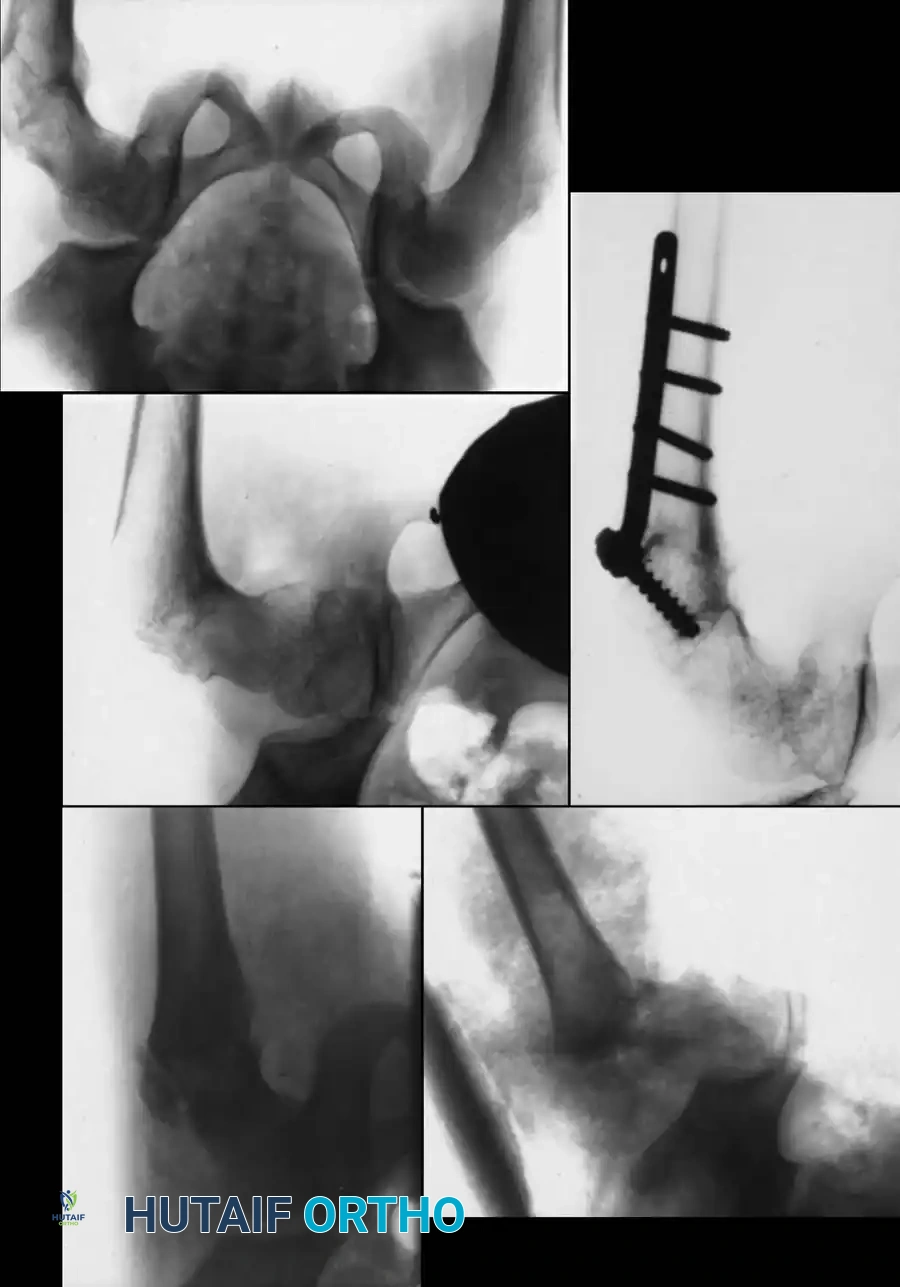

Type III fractures experience massive shear forces. While historically treated with pins, the high rate of varus collapse and nonunion has shifted the paradigm toward more rigid constructs.

- Reduction: Closed reduction on a fracture table.

- Fixation: For "low" cervicotrochanteric fractures, simple screw fixation is often inadequate due to the lack of cortical support inferiorly.

- Technique: Utilize a pediatric dynamic hip screw (DHS) or a cannulated screw with an attached side plate. This converts shear forces into compressive forces and rigidly maintains the neck-shaft angle.

Fig. 14: Displaced Type III cervicotrochanteric fracture prior to intervention.

Fig. 15: Intraoperative reduction of the Type III fracture.

Fig. 16: Final fixation utilizing a cannulated screw and attached side plate to neutralize shear forces.

Fig. 17: Alternative fixation strategy using multiple screws for a high cervicotrochanteric variant.